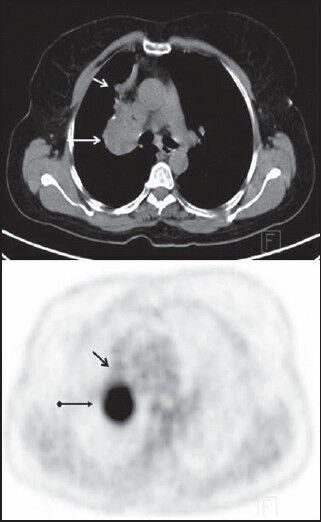

A total of 22 patients with pulmonary carcinoid tumors (14 typical, 8 atypical) were reviewed in this retrospective study. PET/CT images of all patients were evaluated for primary tumor as well as metastatic regional lymph nodes, bone and other distant metastases. PET/CT positivity of primary tumors was determined by visual interpretation. Tumor size, SUVmax and Hounsfield Unit (HU) values of the tumors were used to test for differences between tumor groups (typical carcinoids and atypical carcinoids).

SUVmax of carcinoids ranged from 1.24 to 11.1 (mean, 5.0; median, 2.67). The mean largest diameter of primary tumors was 2.7 ± 1.3 cm, ranging from 1 to 5.5 cm. The overall sensitivity of FDG PET/CT for detection of pulmonary carcinoid tumors was 81.8%. Tumor size, SUVmax and Hounsfield Unit (HU) values of the atypical carcinoids were higher than those for typical carcinoids. However, the results were not statistically meaningful (P > 0.05). The sensitivity and specificity of FDG PET/CT in the detection of mediastinal and hilar lymph nodes metastases were 25% and 83% respectively. One patient had bone metastasis.

Although FDG PET/CT can be a useful tool for the detection of pulmonary carcinoid tumors and distant metastasis, it cannot discriminate typical carcinoids from atypical ones and absence of an FDG avid lesion cannot exclude pulmonary carcinoid tumors. Moreover, PET/CT is not a reliable tool in the staging of mediastinal and hilar lymph nodes especially for those patients with typical carcinoids.